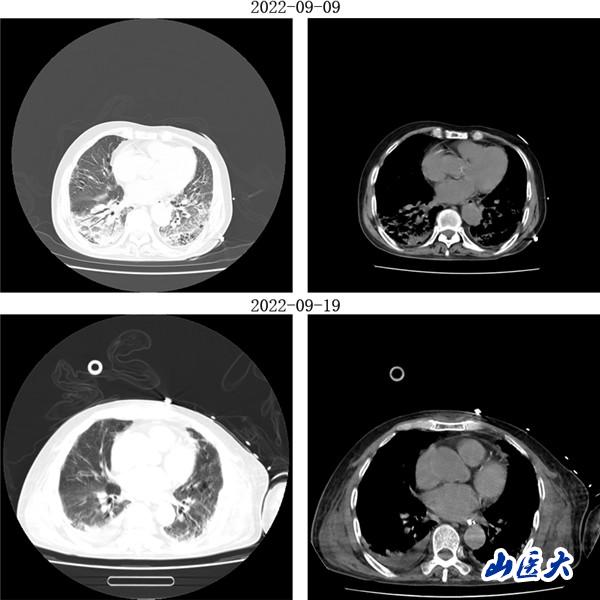

重症医学科三病区张文凯主任团队深入分析了两位患者的病情。考虑到两名老年患者均已出现急性呼吸窘迫综合征,决定采用俯卧位通气技术为他们治疗。在张文凯主任的指导下,侯林义主治医师带领张承、孙洁住院医师对女性患者经俯卧位通气治疗,92小时后复查胸部CT,双肺明显好转,氧合指数由90上升至300mmHg以上,吸氧浓度由100%降至35%,ARDS明显改善;对男性患者,采用联合持续性血液滤过(CRRT)治疗方案,经俯卧位通气治疗66小时后复查胸部CT,显示明显改善,同时氧合指数由102上升至360mmHg左右,吸氧浓度需求下降至40%,全身水肿情况也明显减退。

(女性患者治疗前后胸部CT对比)

(男性患者治疗前后胸部CT对比)